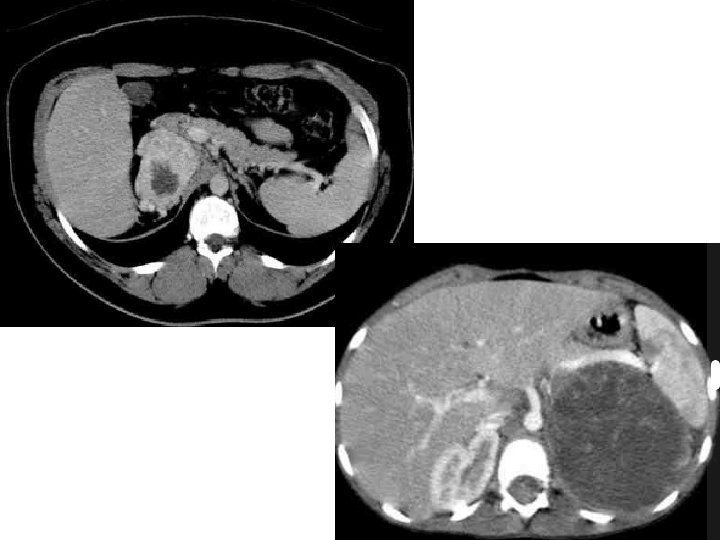

• TK z kontrastem • MRI – Ciąża – Naciek dużych żył • USG – Monitorowanie przerzutów w wątrobie • PET z 18 -FDG (? ) DCMW <50% >35 HU